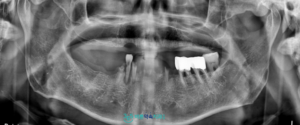

환자분은 60대 남성으로,

전체 임플란트를 고려하시어

본원 환자분의 소개를 통해

전라남도 보성군 벌교읍에서

내원해 주셨습니다.

먼저 구강 내 상태를

확인해 보았더니,

다수 치아가 상실되어 있었으며,

잔존 치아들도 충치와 잇몸 질환으로 인해

예후가 좋지 않았습니다.

정밀한 진단을 위해

파노라마 사진을 촬영한 결과,

남아 있던 치아들은

모두 심한 잇몸 질환의 영향을 받고 있었고,

치아를 지지하는 잇몸 조직도

많이 약해진 상태였습니다.

또한 치아의 흔들림도

큰 편이어서 발치가 불가피한 상황으로

판단되었습니다.

이 경우 전체 치아를

상실하게 되므로 전체 틀니나

전체 임플란트와 같은 방향을 고려할 수 있는데,

환자분께서는 전체 임플란트를

원한다고 말씀해 주셨습니다.